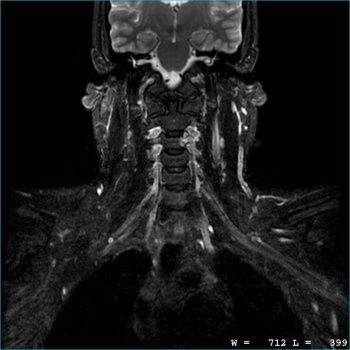

What We Do – MRI

Magnetic resonance imaging (MRI) is a detailed test using a magnetic field and pulses of radio wave energy to make pictures of organs and structures inside the body. An MRI can be used on virtually all areas of the body.

Our advanced imaging equipment allows us to specialize in:

- High Resolution Cross Sectional Imaging

- Musculoskeletal (MSK) Imaging

- Neuroimaging

- IV Contrast Injection